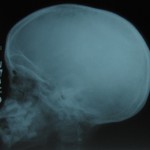

The aim of the site is to present few conventional radiographs which may be helpful to junior practitioners and residents in the speciality of radiology.

Planar imaging is also used in appropriate situations to explain the particular conditions.